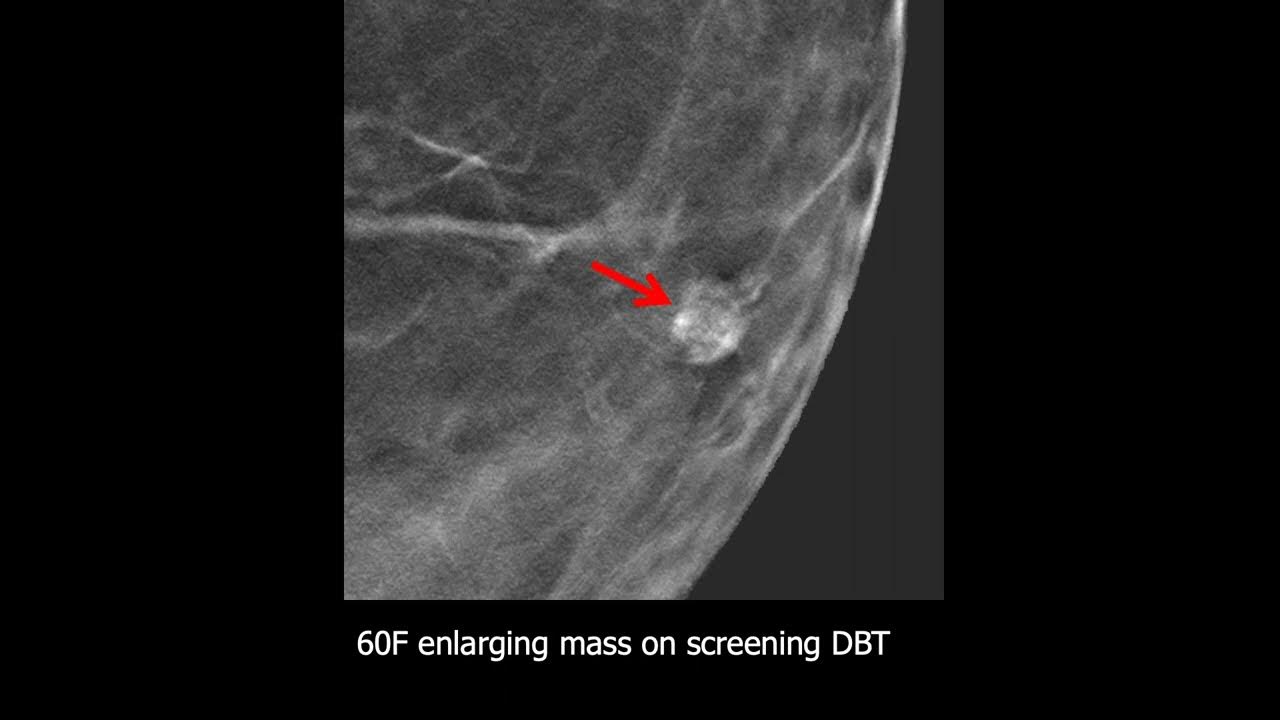

Source: saawtuhtf.pages.dev Comparison of parameters used for BIRADS 4A Download Scientific Diagram , Electronically Signed by: Virginia Molleran, MD, 1/11/2022 3:11 PM Study Result Impression Potentially new 6 x 5 x 4 mm mass at the 11:00 position of the right breast « Vorheriges Thema Nächstes Thema »BI-RADS 4 und OP morgen Brustkrebs